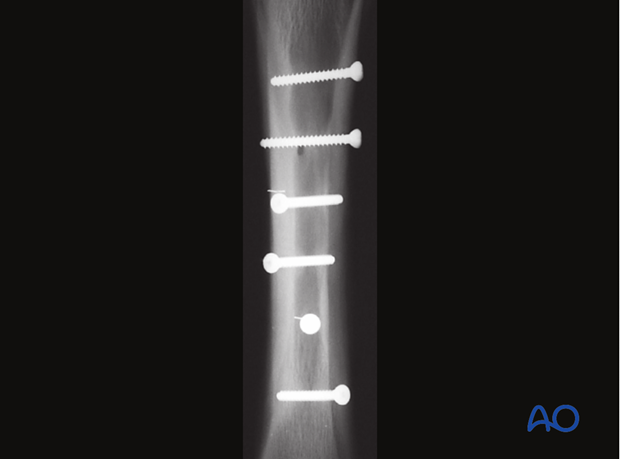

After sterile preparation of the limb, several stainless steel staples should be placed where each screw head is believed to be. Radiographs are then taken so that the exact location of each screw head can be identified. The critical radiographic view for each screw is the one that most closely approximates looking down the shaft of the screw.

Stab incisions are prepared over each screw head and the screw driver fully inserted in the hexagonal heads, so they do not strip. The screws are removed and the stab incisions closed with simple skin sutures.